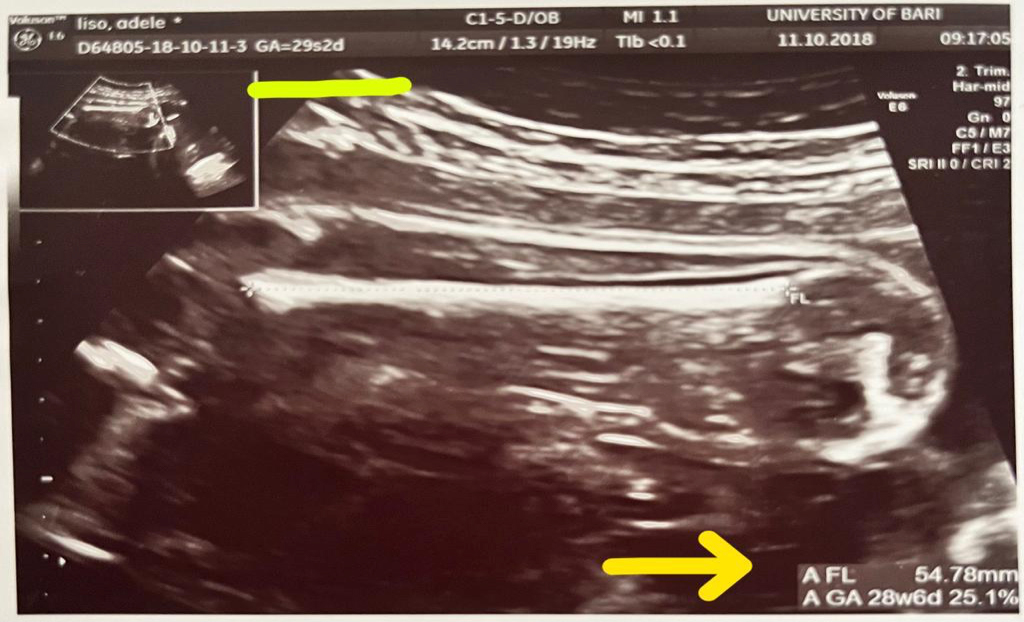

La lunghezza del femore (in millimetri) viene indicata con "FL" su tutte le ecografie.